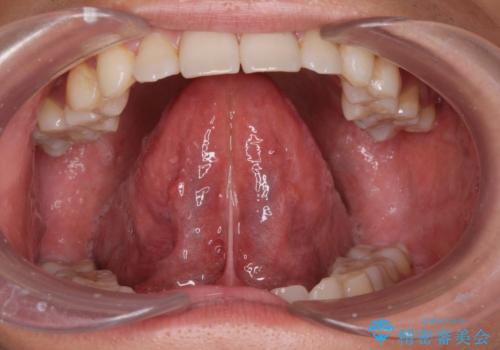

[ 舌小帯の形成術 ] 「ら行」や「た行」が発音しづらいのを改善したい!

担当医 大元洋佑

![[ 舌小帯の形成術 ] 「ら行」や「た行」が発音しづらいのを改善したい!の症例 治療前](https://seimitsushinbi.jp/wp/wp-content/uploads/2023/12/7d9ac5f7c2f3679a481af9859a64f532-500x350.jpg?v=1701830486)

![[ 舌小帯の形成術 ] 「ら行」や「た行」が発音しづらいのを改善したい!の症例 治療後](https://seimitsushinbi.jp/wp/wp-content/uploads/2023/12/999705bbf9ee513b86dbb3839372e65b-500x350.jpg?v=1701830502)